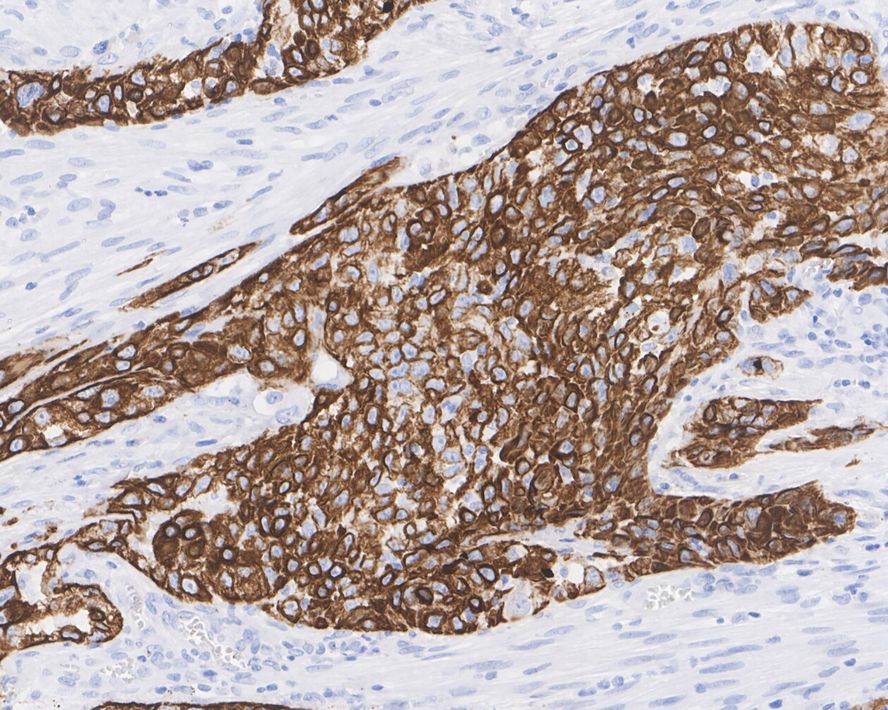

Cytokeratin 17 Recombinant Mouse Monoclonal Antibody [A2B10-R]

IHC-P

Human